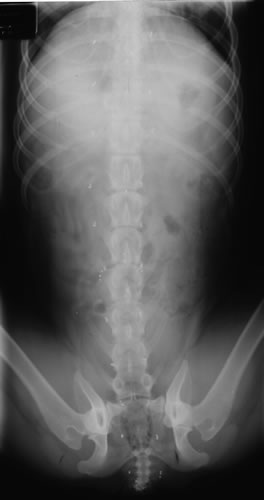

In December 2000, while visiting relatives in California, Korie developed a urinary tract infection. To verify that she did not have bladder stones, the veterinarian in San Jose took an X-ray to confirm or refute the bladder stone theory. Shown here is that X-ray and it very clearly shows her gold beads.